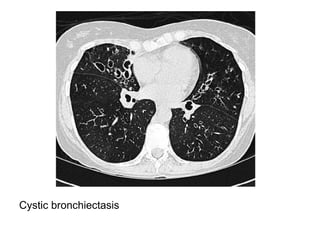

Cystic bronchiectasis